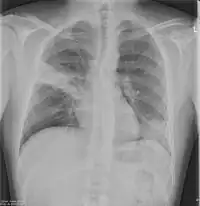

Chest X-rays and X-ray computed tomography (CT) can reveal areas of opacity (seen as white), indicating consolidation.[13] CAP does not always appear on x-rays, sometimes because the disease is in its initial stages or involves a part of the lung not clearly visible on x-ray. In some cases, chest CT can reveal pneumonia not seen on x-rays. However, congestive heart failure or other types of lung damage can mimic CAP on x-ray.[15]

When signs of pneumonia are discovered during evaluation, chest X-rays and examination of the blood and sputum for infectious microorganisms may be done to support a diagnosis of CAP. The diagnostic tools employed will depend on the severity of illness, local practices and concern about complications of the infection. All patients with CAP should have their blood oxygen monitored with pulse oximetry. In some cases, arterial blood gas analysis may be required to determine the amount of oxygen in the blood. A complete blood count (CBC) may reveal extra white blood cells, indicating infection.